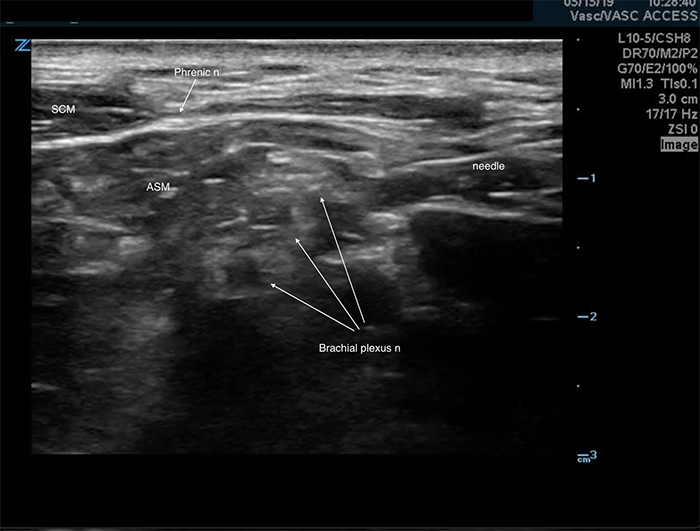

- The ipsilateral phrenic nerve overlies the anterior scalene muscle near the interscalene space. (Figure 4) It is affected during an interscalene nerve block,5 suspected to occur via anterior spread of the anesthetic. Although this complication is associated with a significant reduction in pulmonary function tests,5,6 it is well tolerated in most healthy patients.5,6 Care should be taken in patients with respiratory compromise or underlying lung disease.

Figure 4. Phrenic nerve